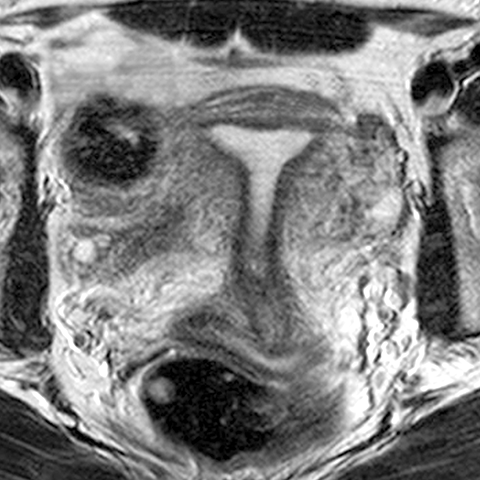

Uterus (T2 weighted MR, coronal) [3 of 4]